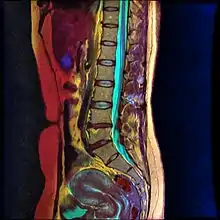

Magnetic Resonance Image of Lumbar Spine courtesy of Nevit Dilmen

Lumbar sympathetic neurolysis is performed between the L1-L4 vertebrae with separate injections at each vertebra junction. The chemicals used for neurolysis of the nerves cause destructive fibrosis and cause a disruption of the sympathetic ganglia. The vasomotor tone is decreased in the area affected by the neurolysis, which in addition to arteriovenous shunting, create a light pink appearance within the affected area. Lumbar sympathetic neurolysis alters the ischemic rest pain transmission by changing norepinephrine and catecholamine levels or by disturbing afferent fibers. This procedure is mainly used only when other feasible approaches to pain management are unable to be used.[6]

Lumbar sympathetic neurolysis is performed by using absolute alcohol, but other chemicals such as phenol, or other techniques such as radiofrequency or laser ablation have been studied. To aid in the procedure, fluoroscopy or CT guidance is used. Fluoroscopic guidance is the most frequent, giving better real-time monitoring of the needle. The general technique of administering lumbar sympathetic neurolysis involves using three separate needles rather than one because it allows for better longitudinal spread of the chemicals.[6]